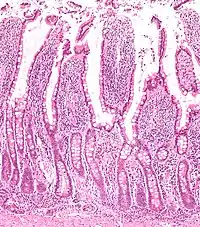

Tracing has revealed that LGR5 is a marker of adult intestinal stem cells. The high turnover rate of the intestinal lining is due to a dedicated population of stem cells found at the base of the intestinal crypt. In the small intestines, these LGR5+ve crypt base columnar cells (CBC cells) have broad basal surfaces and very little cytoplasm and organelles and are located interspersed among the terminally differentiated Paneth cells.[12] These CBC cells generate the plethora of functional cells in the intestinal tissue: Paneth cells, enteroendocrine cells, goblet cells, tuft cells, columnar cells and the M cells over an adult's entire lifetime. Similarly, LGR5 expression in the colon resembles faithfully that of the small intestine.[12]